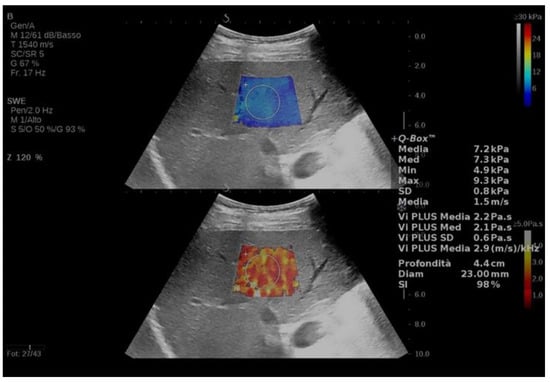

- Popa, A.; Sporea, I.; Bende, F.; Popescu, A.; Fofiu, R.; Borlea, A.; Bâldea, V.; Pascu, A.; Foncea, C.G.; Cotrău, R.; et al. The Non-Invasive Ultrasound-Based Assessment of Liver Viscosity in a Healthy Cohort. Diagnostics 2022, 12, 1451. [Google Scholar] [CrossRef] [PubMed]